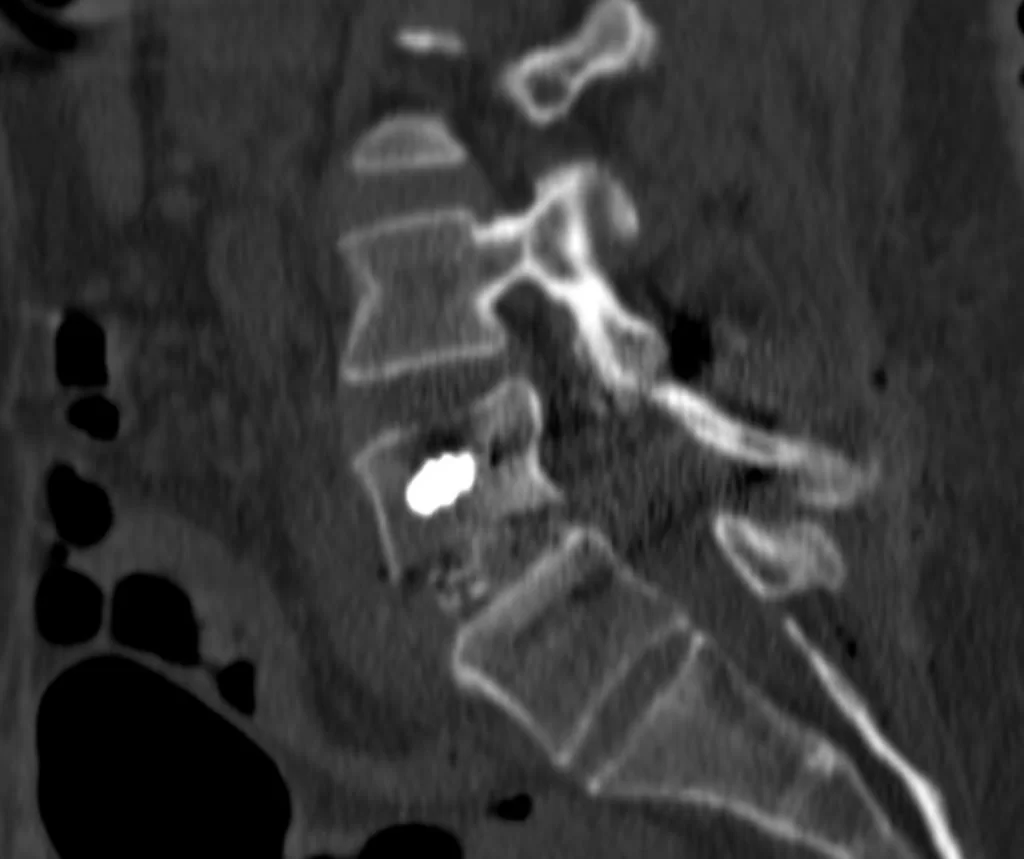

Ο απεικονιστικός έλεγχος ανέδειξε σπονδυλολίσθηση 2ου βαθμού σε έδαφος σπονδυλόλυσης (λύση της συνέχειας του οστού στον ισθμό, δηλαδή μεταξύ των δύο αρθρώσεων).

Διενεργήθη διαδερμική (ελάχιστα επεμβατική) σπονδυλοδεσία στο επίπεδο Ο4/Ο5